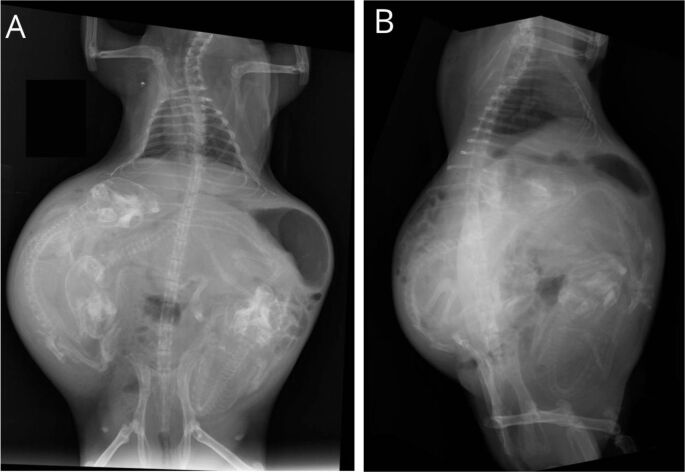

Dystocia is a common complication in guinea pig pregnancies, presenting significant challenges in clinical management. The present case report describes the presentation, diagnosis, and surgical intervention in an 8 months old female guinea pig with dystocia. The subject is a primiparous guinea pig originating from a commercial breeder, exhibited prolonged labor with two pups, one of which was stillborn. Physical examination revealed a distended abdomen, lack of uterine contractions, signs of distress, and vulvar discharge. Radiographic and ultrasound tests confirmed obstruction due to large fetal size and mineralization of the pubic symphysis. Surgical intervention proceeded with a ventral midline approach, ovariohysterectomy and removal of three fetuses. The guinea pig recovered well from the procedure, being discharged with postoperative care, and the use of anti-inflammatory, analgesics, prokinetics, antibiotics as well as scopolamine. The objective of the present work is to discuss and emphasize the importance of veterinary intervention, diagnostic evaluation and therapeutics for the multifactorial nature of dystocia management. Despite the surgical treatment, the prognosis for both dam and offspring remains guarded, highlighting the need for early detection and intervention to optimize outcomes in guinea pig dystocia cases.